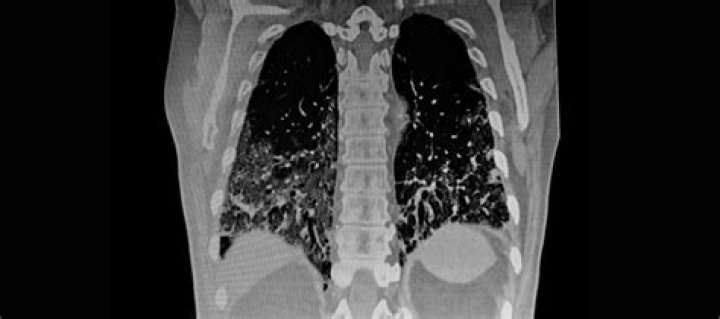

Read JournalCT technology is used to detect pulmonary nodules, collections of abnormal tissue in the lungs that may be early manifestations of lung cancer. These nodu...